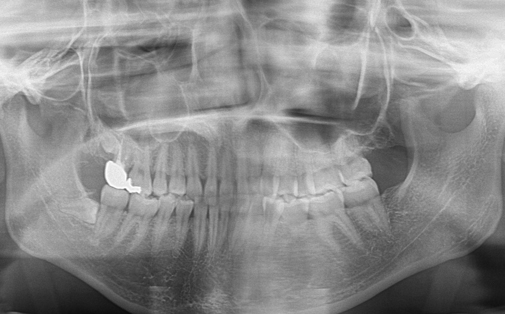

Before

After

左上の歯が折れています。折れた歯を抜き、親知らずの歯を移植しました。